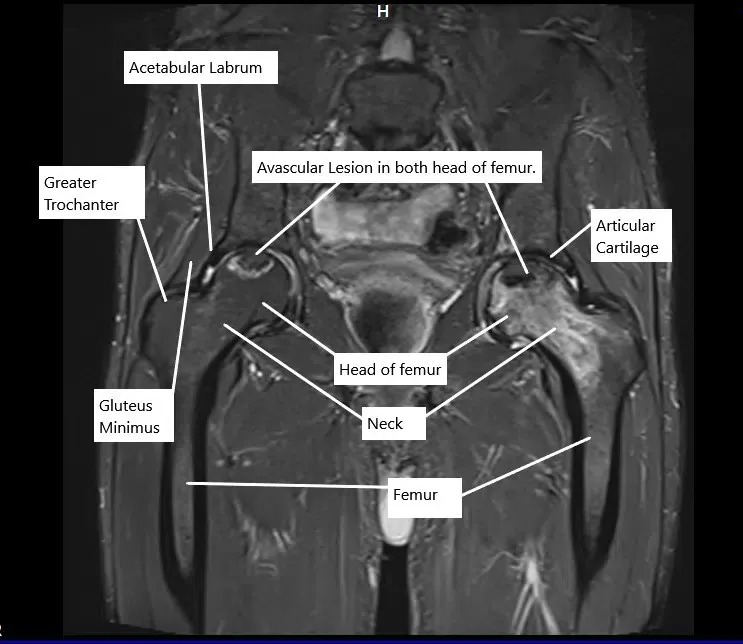

Resonancia magnética en la sección coronal que muestra lesiones de necrosis avascular en ambas caderas

La necrosis avascular ocurre como resultado de la muerte ósea en la cabeza del fémur. La muerte ósea ocurre debido a la interrupción del suministro sanguíneo de la cabeza del fémur. La interrupción del suministro sanguíneo puede producirse como resultado de un traumatismo directo en la cadera. Las luxaciones y fracturas traumáticas de cadera se asocian comúnmente con necrosis avascular de la articulación de la cadera.